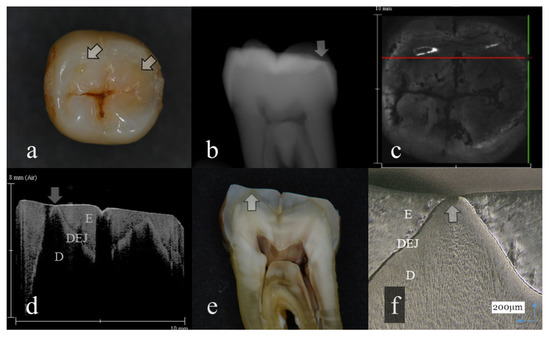

Figure 4.

Tooth wear with slight dentin exposure (score 3); (a): Occlusal view. Occlusal cusps were flattened. The middle of the cusp was collapsed showing the small dent (arrow); (b): Digital intraoral radiography. Remaining enamel thickness of all the tooth crown was extremely reduced (arrow); (c): OCT en face intensity projection; (d): SS-OCT image. Occlusal enamel was worn, showing the flattened surface. Loss of enamel reached to the DEJ with slight dentin exposure (arrow). The brightness of the exposed dentin surface was increased, suggesting dentin demineralization (arrow); (e): Histological view. Enamel thickness for all the tooth crown was thin. Occlusal tooth wear involved slight dentin exposure (arrow); (f): CLSM image of histological view. Slight dentin exposure at the cusp was observed (arrow). The corresponding dynamic slicing 3D video is in Supplementary Materials: Video S4. The upper right is a cross sectional view. Lower right is an en face image.

Three-dimensional OCT could detect the presence of dentin exposure within the tooth wear surface with pinpoint accuracy (Figure 3, Figure 4, Figure 5, Figure 6 and Figure 7, Videos S3–S7). Since dentin exposure may cause DH in response to mechanical and chemical stimuli during masticatory function, accurate diagnosis for dentin involvement appears beneficent for further maintenance and an intervention approach. Dentin contains 50 vol% of organic structure and scatters light, and signal attenuation of the OCT image through the dentin is higher than the enamel [29]. Optical dissimilarity between the two structures facilitates the discrimination of the tooth wear with and without dentin involvement. In this study, 3D OCT could clearly image the dentin exposure within the tooth wear surface, resulting in high diagnostic capacity and accuracy (Table 1, Table 2 and Table 3). OCT could also facilitate the characterization of exposed dentin surface changes, including the formation and thickness of transparent dentin [29].

In OCT, some of the samples with distinct tooth wear showed increased brightness at the superficial enamel or dentin, suggesting the presence of surface demineralization (Figure 4, Figure 6 and Figure 7) [16,17]. The incidence of demineralization was associated with tooth wear involving dentin (level 4) in many cases. Meanwhile, as the history of extracted teeth was unknown in this study, increasing the frequency of tooth demineralization with the advancement of tooth wear level may suggest the risk of erosion and ETW to facilitate tooth loss to the pathological level. Moreover, it is noteworthy that OCT could detect the enamel crack associated with tooth wear (Figure 6). This finding also showed increasing frequency with the advancement of tooth wear level. In this study, 11 cases out of 29 samples of level 4 dentin exposure showed distinct enamel crack penetrating into DEJ, and 2 cases of 29 samples showed slight enamel crack limited within the enamel thickness.